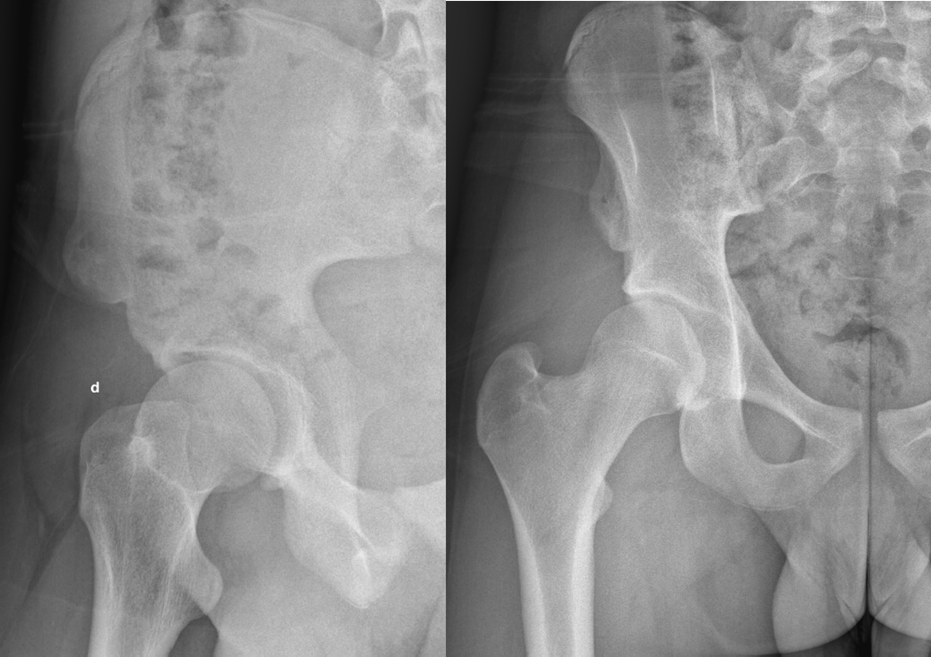

Standard pelvic radiography revealed a displaced bony fragment at the right AIIS. CT scan confirmed the avulsion fracture without intra-articular involvement or adjacent soft tissue injury.

Figure 1. Initial radiograph of the right hip: epiphyseal separation of the anterior inferior iliac spine.

Figure 3. X-ray of the right hip 1 month post-traumatic.

Figure 4. X-ray of the right hip 8 months post-traumatic.